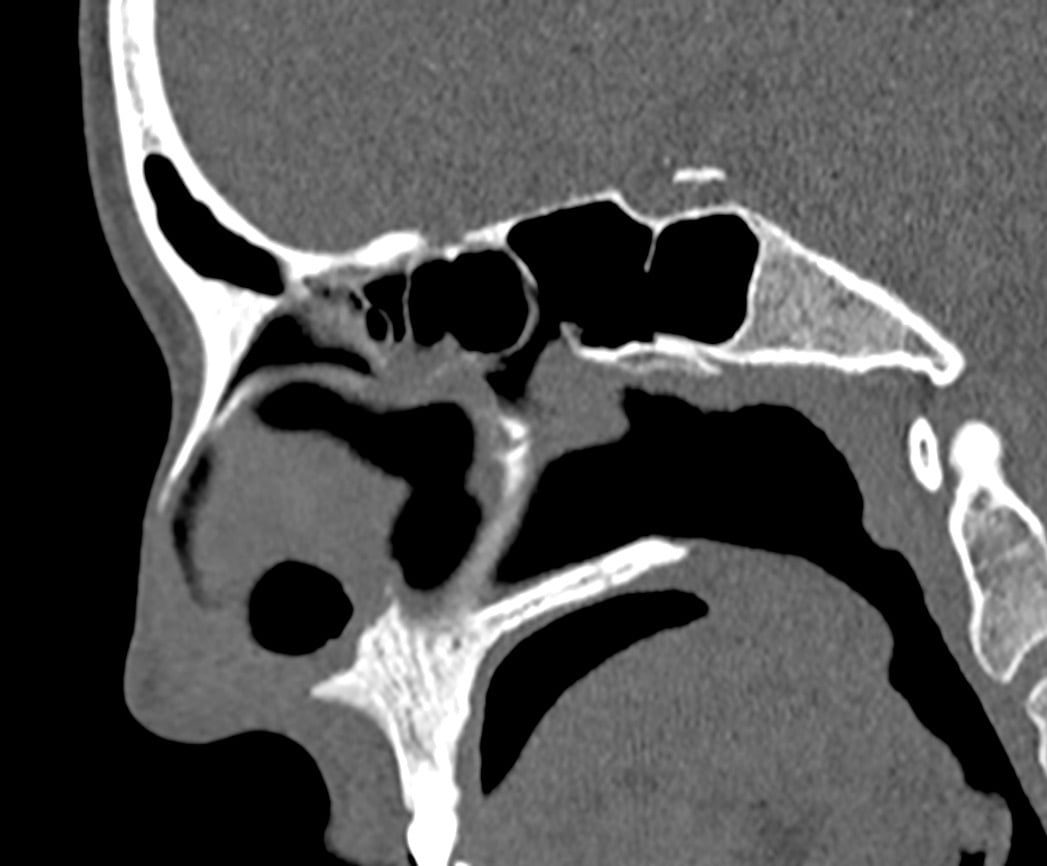

Perforacija septuma jedna je od poznatih, ali relativno rijetkih komplikacija operacija nosa. Najčešće se povezuje sa septoplastikom, ali može nastati i nakon rinoplastike ili endoskopske kirurgije sinusa.Iako je učestalost mala, posljedice mogu biti dugotrajne i funkcionalno značajne – osobito ako se defekt nalazi u prednjem dijelu septuma.

Nosna pregrada obložena je sluznicom s obje strane. Tijekom operacije kirurg pažljivo odvaja sluznicu kako bi ispravio devijaciju ili pristupio dubljim strukturama.

Hrskavica septuma nema vlastitu krvnu opskrbu – ovisi o sluznici. Ako obje strane sluznice izgube vitalnost, dolazi do nekroze hrskavice i stvaranja trajnog defekta.